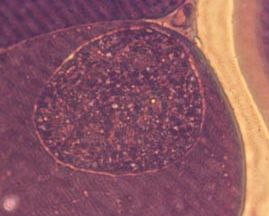

病変は小腸下部から盲・結腸にみられる粘膜病変であり、カタール性・出血性腸炎、粘膜肥厚、出血などが、また、シゾントが小白斑としてみられます。

重症例では粘膜に潰瘍もみられ、腸管内には血液や、血液と混ざった内容物が存在します。本症は、数か月齢から1歳までの子牛が発症しやすい。

前者は盲腸に寄生し、粘膜に出血、壊死、上皮剥離をみる出血性腸炎を生じ、盲腸内は血液、壊死組織が混ざった凝固物、滲出物で充満し拡張してみられる。

後者は主として小腸の中・後部に寄生し、小腸粘膜にE.tenellaに類似した病変を生じます。他の種類はいずれも小腸に寄生しますが、病原性が弱く、軽度感染では病変は明らかでなく、重度感染によって軽度なカタール性腸炎を生じますが、出血性変状は一般にみられないか軽微です。